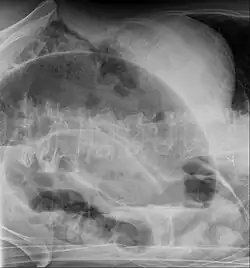

After taking a thorough history, the diagnosis of colonic volvulus is usually easily included in the differential diagnosis. Abdominal plain x-rays are commonly confirmatory for a volvulus, especially if a coffee bean sign is seen. These refer to the shape of the air-filled closed loop of the colon, which forms the volvulus. Should the diagnosis be in doubt, a barium enema may demonstrate a "bird's beak" at the point where the segment of proximal bowel and distal bowel rotate to form the volvulus.

This area shows an acute and sharp tapering and looks like a bird's beak. If a perforation is suspected, barium should not be used due to its potentially lethal effects when distributed throughout the free intraperitoneal cavity. Gastrografin, which is safer, can be substituted for barium.

An x-ray of a person with a small bowel volvulus.

Plain X ray of a cecal volvulus -